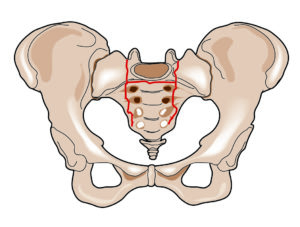

Pelvic fractures, also known as insufficiency fractures, are common osteoporotic fractures of the pelvis and are often overlooked or misdiagnosed. The most common of these pelvic fractures involves the sacrum, known as a sacral insufficiency fracture. Although other parts of the pelvis may suffer similar fractures, this article describes the symptoms, diagnosis, and available treatments for sacral insufficiency fractures.

In a sacral insufficiency fracture, the bone is weakened, usually from osteoporosis, to the extent that it gives way with only body weight or minimal trauma. Sacral insufficiency fractures have existed as long as osteoporosis but have received less attention than back and hip fractures. In fact, this condition was only first described in literature in 1982.(1) One reason this diagnosis was not recognized is the nonspecific, but sometimes severe, symptoms. The symptoms overlap with that of other low back problems, such as disc herniation, facet arthritis, and compression fractures.For example: When an elderly patient presents to the emergency room, the first test usually ordered by an ER physician is an X-ray. When testing for a sacral insufficiency fracture, an X-ray will almost always be normal. Since the X-ray result is “negative,” the patient is often sent home or even kept in the hospital with continued pain and no diagnosis.

Sacral insufficiency fractures are difficult to diagnose. When a previously active elderly patient, more commonly a female, presents with severe new pain in one or both buttocks and is unable to move about, the patient should be considered to have a sacral insufficiency fracture until proven otherwise. Symptoms are often insidious with no known event. Other times, symptoms start after a minor fall on the buttocks, a misstep off a curb, or sitting down too hard. The pain may radiate to the groin or down the back of the leg.

An MRI is the best test to diagnose a sacral insufficiency fracture. Often, however, a routine lumbar MRI is ordered, which includes only a small upper portion of the sacrum. If a patient is not able to have an MRI, a CT is the second best test to diagnose the fracture. Even with a CT test, a sacral insufficiency fracture can be very subtle and often missed, unless there is a high index of suspicion by the radiologist. Another test to diagnose a sacral insufficiency fracture is the radionuclide bone scan. Radionuclide bone imaging is sensitive for these fractures but unfortunately does not show the actual fracture, just the abnormal bony activity or “hot spot.”

Sacroplasty as a treatment for sacral insufficiency fractures was first described in 2002.(2) The procedure is an extension of vertebroplasty and kyphoplasty, which have gained acceptance as treatments for vertebral compression fractures. Injection of bone cement into a vertebral compression fracture originated in France in 1987,(3,4) but was not popularized until the 1990s in the United States.(5) Sacroplasty lagged behind in popularity for several reasons. One of these reasons is that sacral insufficiency fractures were less likely to be recognized and were thought to be shear fractures as opposed to compression fractures. A second reason is the technique of sacroplasty is more technically challenging due to the complex shape of the sacrum.

Sacroplasty is performed as an outpatient procedure with minimal to no sedation. Using local anesthesia, a needle is placed into the largest part of the sacrum called the sacral ala. This can be performed with fluoroscopic or CT guidance; both methods have advantages. Once the needle is in the proper location, polymethylmethacrylate (PMMA – bone cement) is mixed and slowly injected into the fractured area. The cement hardens within an hour. The patient lies prone or supine for the hour after the procedure. Once the hour passes, the patient may ambulate, usually with much less pain than before the procedure.